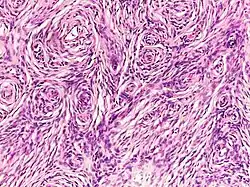

Histopathology of neurofibroma: A spindle cell lesion composed of slender fibroblast-like cells with storiform pattern and very low amount of stroma.[13]